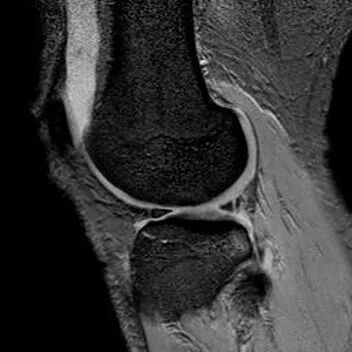

半月板斜行撕裂

最常见类型:斜行撕裂表现为:在矢状面上见III级高信号到达半月板关节面的上缘或下缘